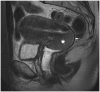

Magnetic resonance imaging is the optimal modality for pelvic imaging. It is based on T2-weighted magnetic resonance (MR) sequences allowing uterine and vaginal cavity assessment as well as rectal evaluation. Anatomical depiction of these structures may benefit from distension, and conditions either developing inside the lumen of cavities or coming from the outside may then be better delineated and localized. The need for distension, either rectal or vaginal, and the way to conduct it are matters of debate, depending on indication for which the MR examination is being conducted. In this review, we discuss advantages and potential drawbacks of this technique, based on literature and our experience, in the evaluation of various gynecological and rectal diseases.